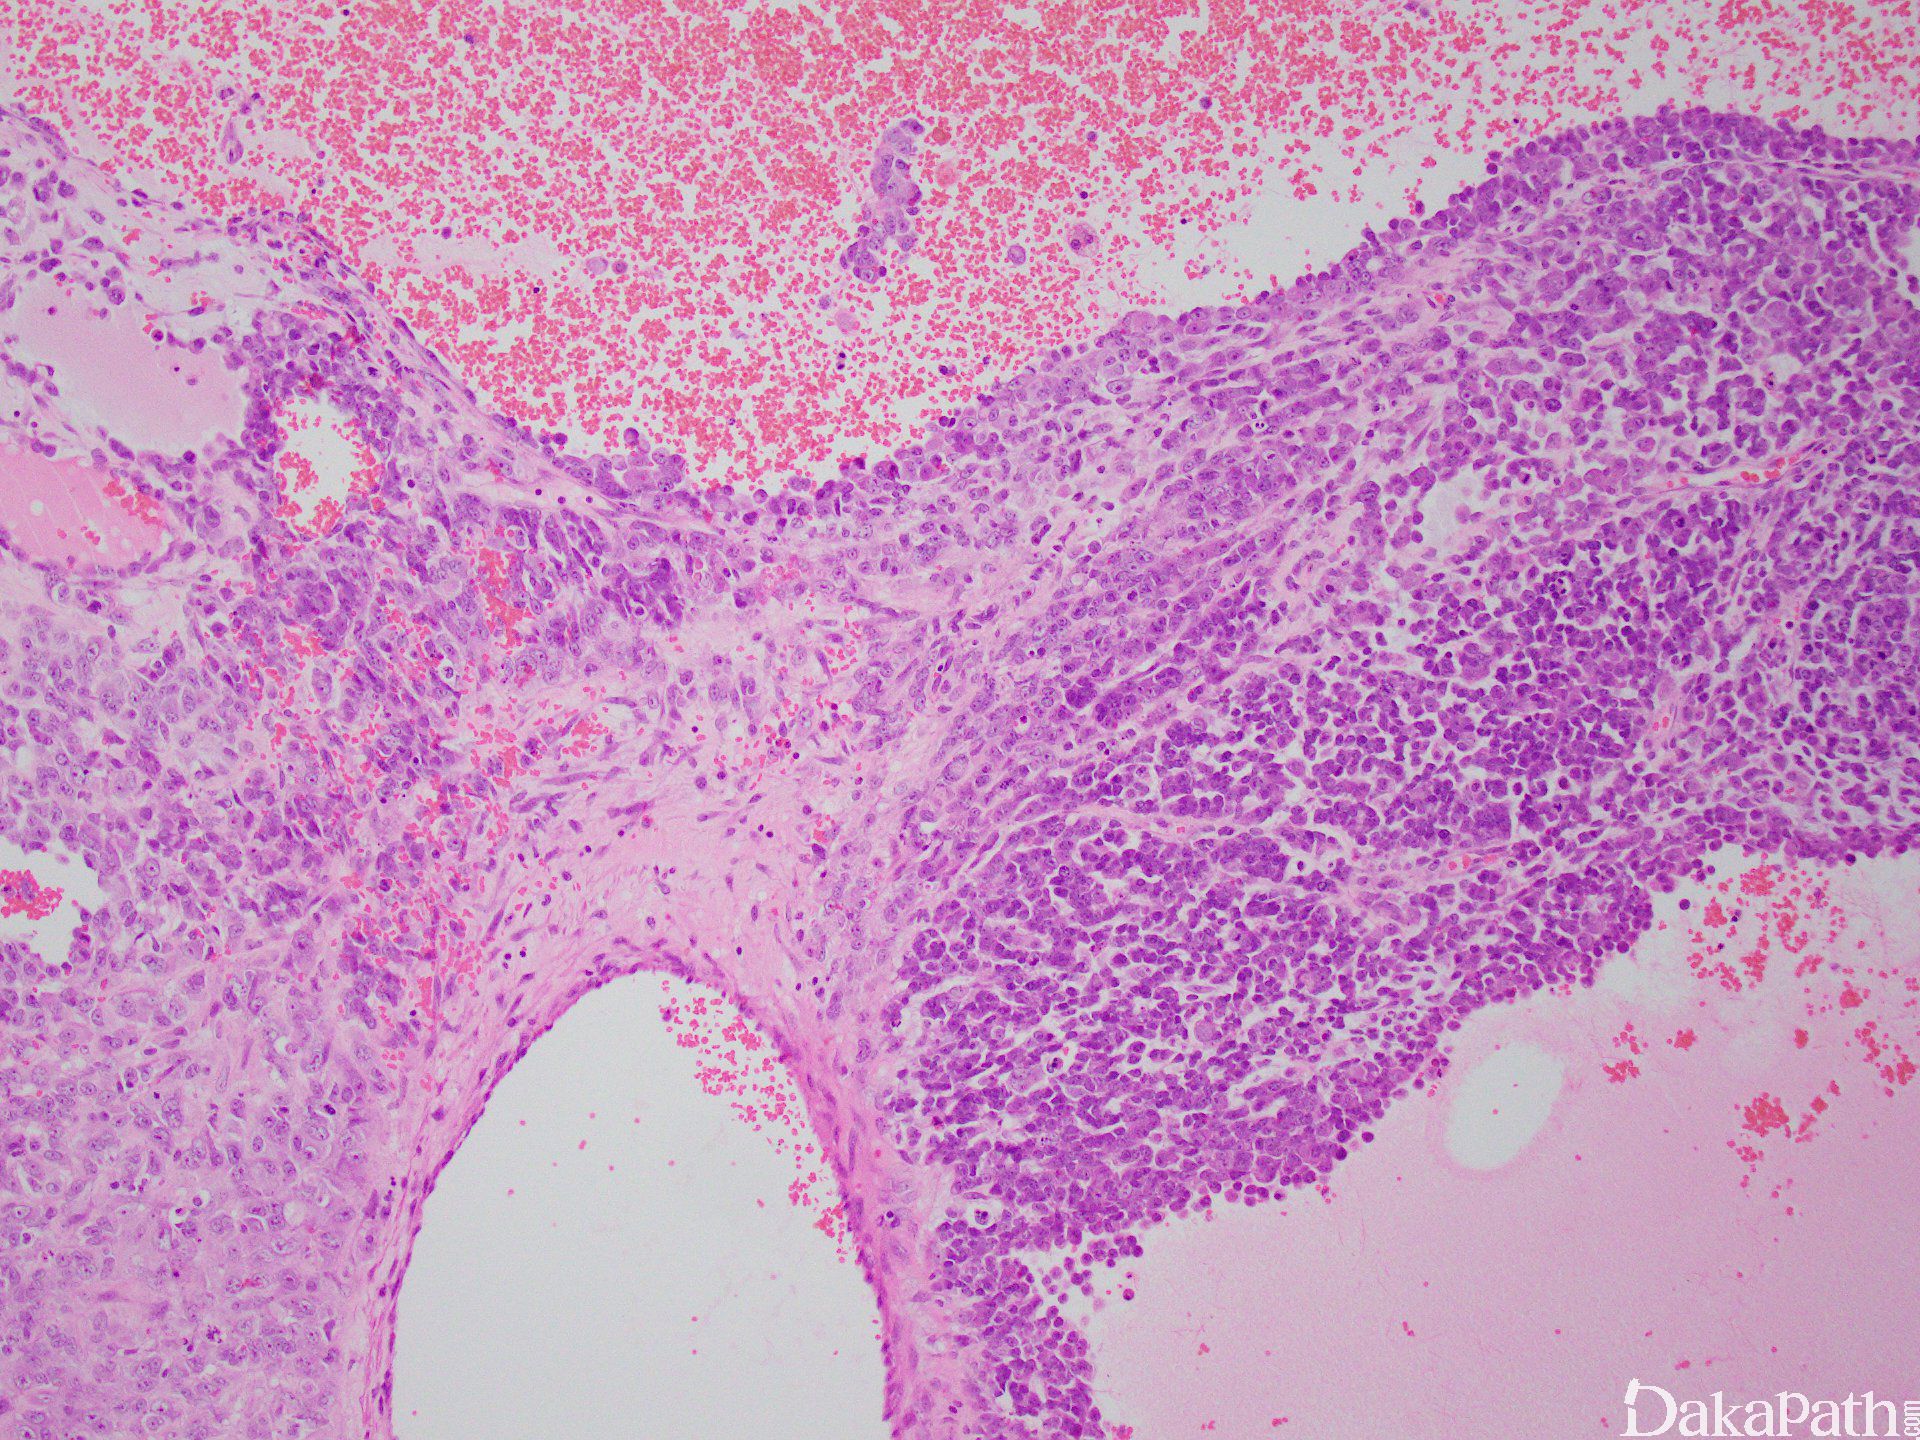

2.肿瘤细胞呈弥漫片状、密集拥挤的巢状分布,有时呈岛状、小梁状、菊型团样及腺样构型;

3. 细胞小或中等大,圆形至短梭形,胞质少,核深染,染色质似胡椒粉状,核分裂像多见, 坏死常见;

4. 多数病例有普通上皮成分如子宫内膜样癌、黏液癌;